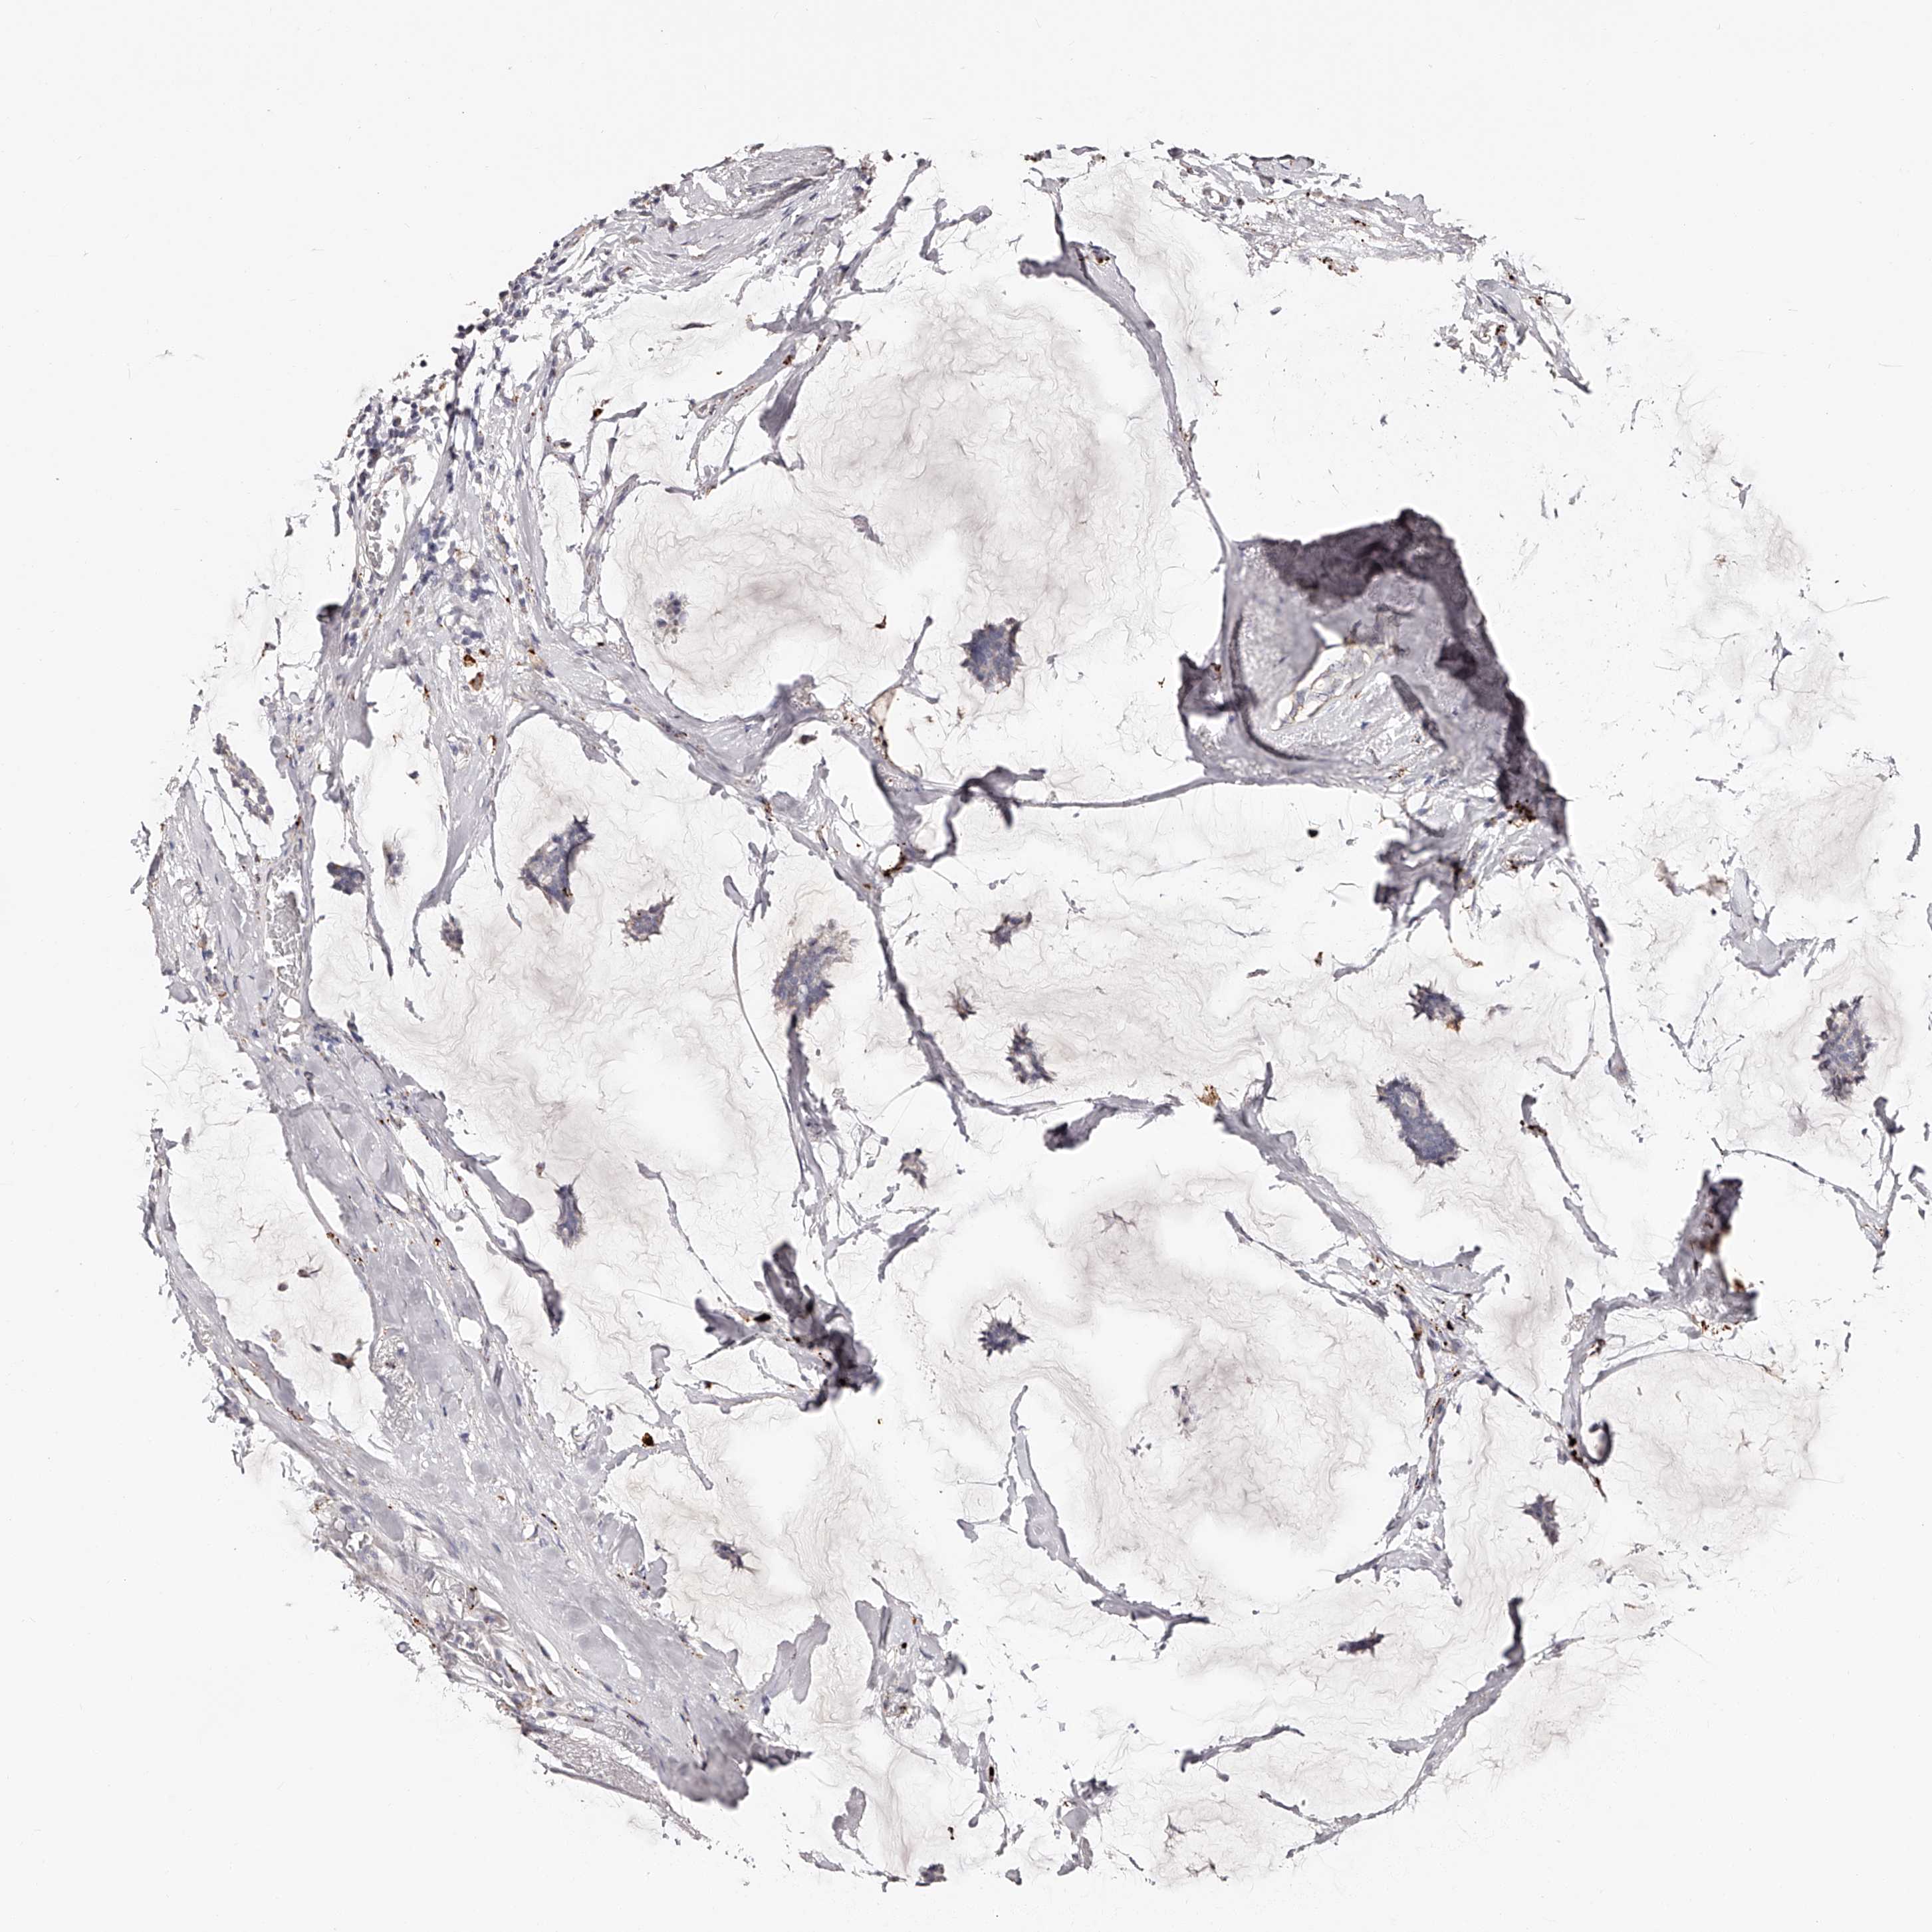

CANCER BREAST CANCER Show tissue menu

Breast cancer

Human cancer

SLC35D3 is not prognostic in Breast Invasive Carcinoma (TCGA)